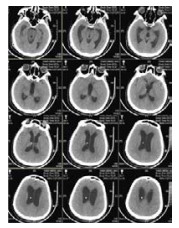

病例4,男,26岁,因“车祸致颅脑损伤昏迷6个月”而入我院。急诊行开颅血肿清除术后1个月因脑积水而行V-P分流术。入院体检:GCS 7分,植物状态,四肢肌张力高,双巴氏征阳性。入院诊断为:重型颅脑损伤术后,脑积水V-P分流术后,持续性植物状态(图 6A)。考虑V-P分流过度引流,将分流调压阀调至最高的2.5水平,骨窗压力和头颅CT没有明显改变。遂将分流管皮下缝扎完全阻断,骨窗压力逐渐升高,术后复查CT(图 6B), 同时患者意识水平改善至微小意识状态。因脑积水加重再行V-P分流术,并择期予右额颞颅骨修补重建,随访头颅CT见图 6C。随后患者恢复至GCS 15分。

| A:男,26岁,颅脑损伤术后6个月入院时头颅CT;B:2015年1月4日分流管缝扎后CT;C:2017年3月8日V-P分流和颅骨修补术后 图 6 病例4 CT |